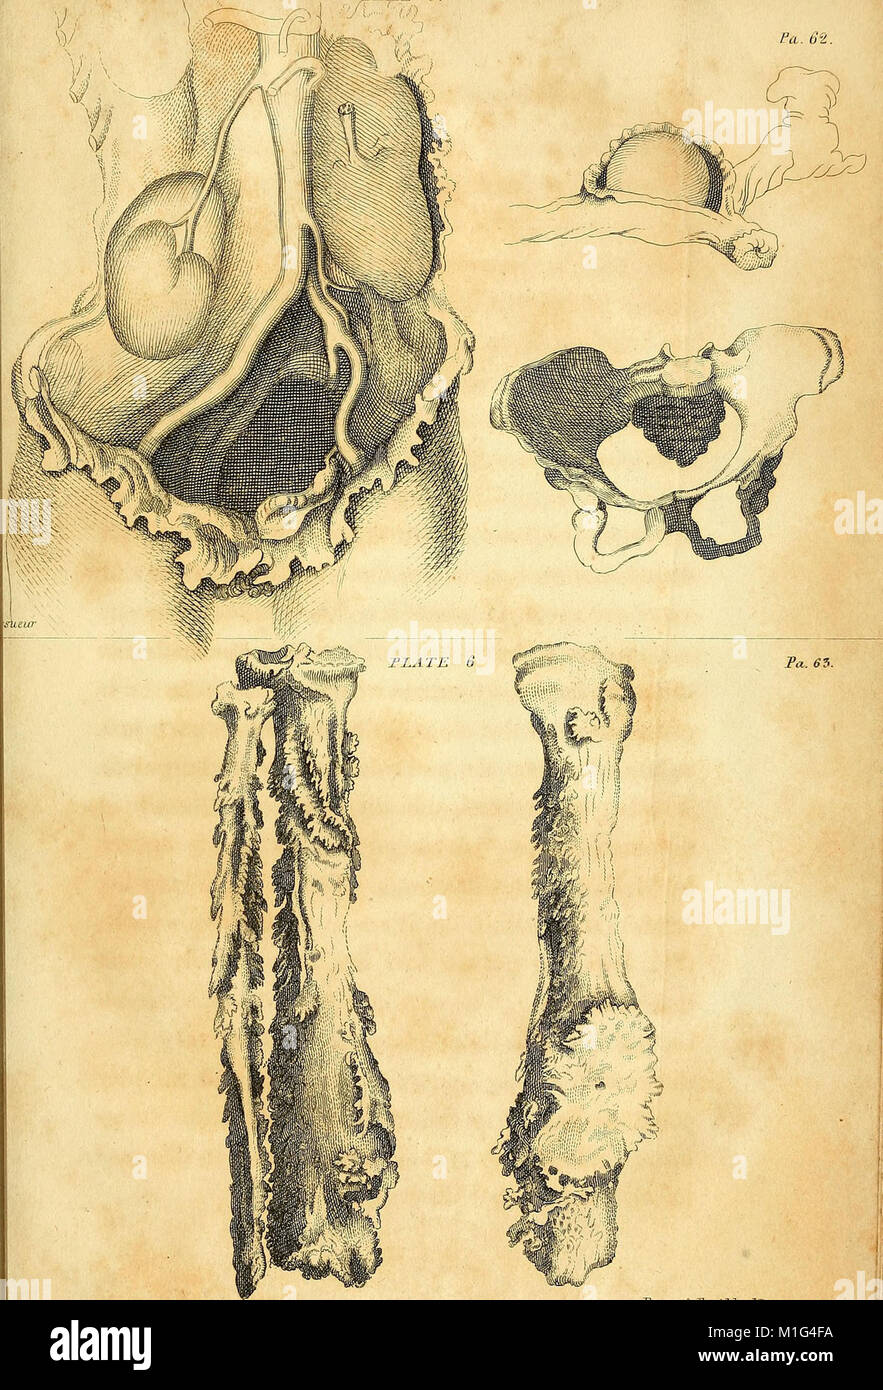

Anatomical investigations, comprising descriptions of various fasciae of the human body to which is added an account of some irregularities of structure and morbid anatomy; with a description of a new (18170837441) Stock Photohttps://www.alamy.com/image-license-details/?v=1https://www.alamy.com/stock-photo-anatomical-investigations-comprising-descriptions-of-various-fasciae-173073168.html

Anatomical investigations, comprising descriptions of various fasciae of the human body to which is added an account of some irregularities of structure and morbid anatomy; with a description of a new (18170837441) Stock Photohttps://www.alamy.com/image-license-details/?v=1https://www.alamy.com/stock-photo-anatomical-investigations-comprising-descriptions-of-various-fasciae-173073168.htmlRMM1G4GG–Anatomical investigations, comprising descriptions of various fasciae of the human body to which is added an account of some irregularities of structure and morbid anatomy; with a description of a new (18170837441)

'Anatomical Investigations' (1798) offers detailed descriptions of human fasciae, irregularities in body structure, and cases in morbid anatomy. It also introduces a new anatomical discovery, contributing to medical understanding of human anatomy. Stock Photohttps://www.alamy.com/image-license-details/?v=1https://www.alamy.com/stock-photo-anatomical-investigations-1798-offers-detailed-descriptions-of-human-173073134.html

'Anatomical Investigations' (1798) offers detailed descriptions of human fasciae, irregularities in body structure, and cases in morbid anatomy. It also introduces a new anatomical discovery, contributing to medical understanding of human anatomy. Stock Photohttps://www.alamy.com/image-license-details/?v=1https://www.alamy.com/stock-photo-anatomical-investigations-1798-offers-detailed-descriptions-of-human-173073134.htmlRMM1G4FA–'Anatomical Investigations' (1798) offers detailed descriptions of human fasciae, irregularities in body structure, and cases in morbid anatomy. It also introduces a new anatomical discovery, contributing to medical understanding of human anatomy.